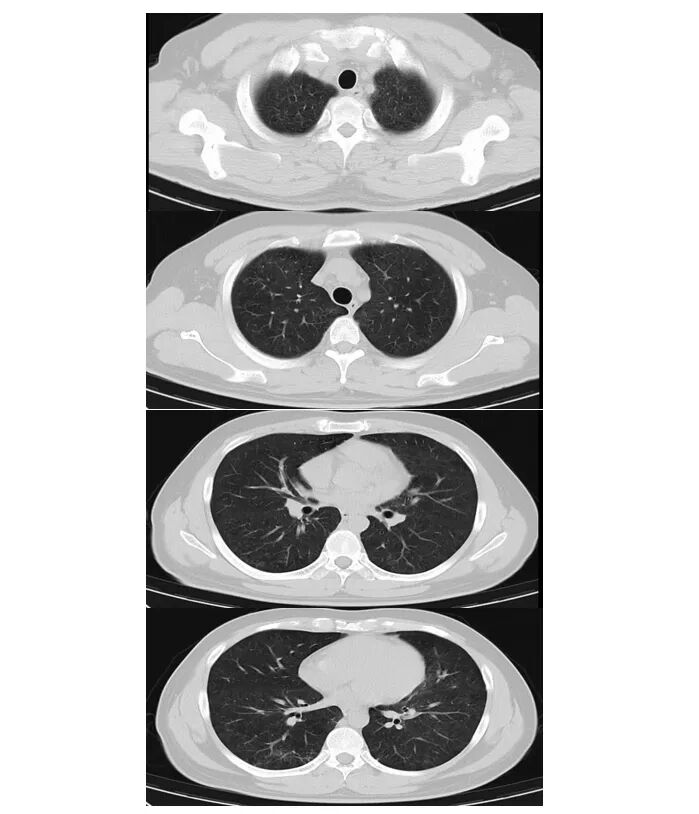

2024年12月27日胸部CT:双肺弥漫性病变

病史特点:青年男性,急性起病,以高热、皮疹为首发症状,Tmax 40℃,基础疾病考虑艾滋病,CD4计数极低。目前在肺孢子菌肺炎治疗期间(影像学示病灶吸收),急性出现高热伴全身弥漫性红色皮疹。发热、皮疹病因暂不明确,具体鉴别如下。

2. 肺孢子菌肺炎:肺泡灌洗液tNGS两次均检出大量耶氏肺孢子菌序列(首次40564条;复查19354条),为确诊依据临床影像吻合:亚急性起病,进行性气促;胸部CT呈典型双肺弥漫性磨玻璃影;针对pjp的治疗(复方磺胺甲噁唑、克林霉素)后,临床症状及影像学明显好转。